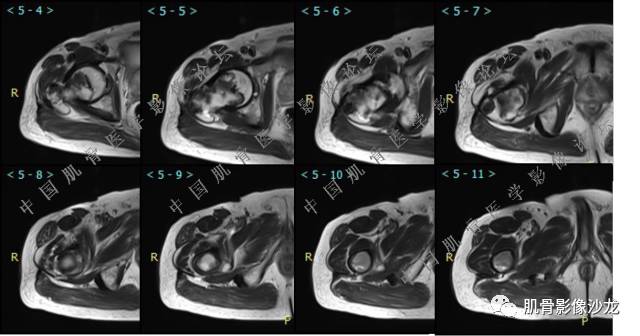

主诉:右髋及右膝部疼痛3月余

现病史:3月前打球时自觉右大腿肌肉拉伤后右髋及右膝部疼痛,自服“活血化瘀”类药物(具体不详)后自觉疼痛缓解,2月前打球时再次扭伤,右髋及右膝部疼痛明显,行走时疼痛加重,自服药物治疗,效果不佳,遂来诊。

葛英霖 20:10 判断恶性程度需要看骨髓内浸润的是肿瘤还是水肿 ,从目前看,骨肉瘤是要考虑的

张小林 20:13 磁共振有双低信号,结合CT确实要考虑有纤维成份。

医影在线 20:13 干骺端溶骨性破坏,边缘模糊,低密度肿块,似有钙化

Echo 20:13 有骨质破坏,边界不清,有软组织肿块,我觉得恶性是要考虑的

Echo 20:23 我个人觉得,17岁男性,病灶发生在原干骺端区域,溶骨性骨质破坏,似有肿瘤骨,有软组织肿块形成,从常见病发生率来说,骨肉瘤还是要考虑的